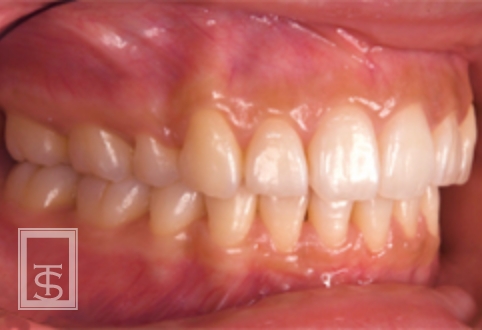

歯軸の重要性

歯軸とは、歯の長軸と上下顎基準平面との角度を意味しています。

審美的改善、機能的安定を獲得するには個人個人に合わせた歯軸の設定が必要です。

また、歯軸の設定は矯正治療時の抜歯判定の基準として用いられます。